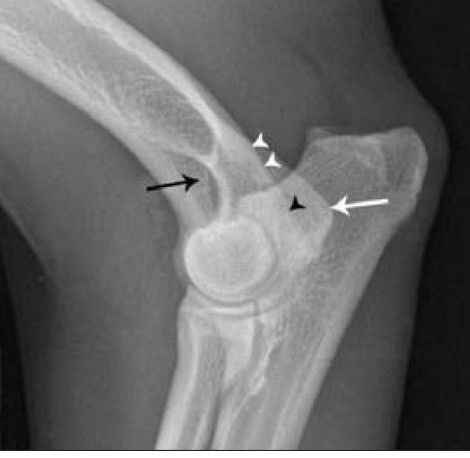

what are the white arrowheads pointing to?

lateral supracondylar crest

what is the black arrowhead pointing to?

caudal aspect of the lateral epicondyle